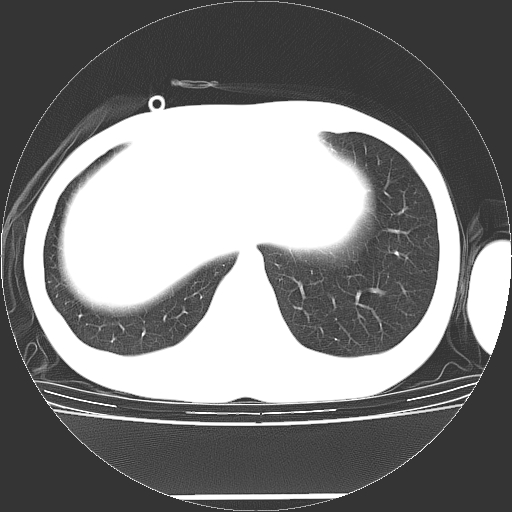

标题: CT19767:男,20岁,右侧气胸行闭式引流术后五天CT检查。 [打印本页]

标题: CT19767:男,20岁,右侧气胸行闭式引流术后五天CT检查。

男,20岁,右侧气胸行闭式引流术后五天ct检查看肺内是否有肺大泡,纵隔窗未见异常,未上传。

未见肺大泡影

右肺未见确切肺大泡。

1)右侧胸腔闭式引流术后导管留置。2)右肺未见肺大泡。

未见肺大泡,还有微量气体。